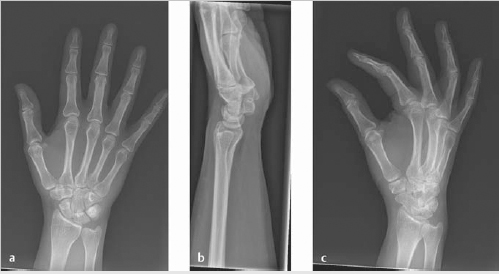

II. Radiograph Views

Three view of the wrist should be obtained: Posteroanterior (PA), lateral, and oblique views (► Fig. 3.2).

Posteroanterior (PA) view—obtained with wrist and elbow at shoulder height; the radius and the ulna are parallel (► Fig. 3.2a).

Able to see the extensor carpi ulnaris groove radial to the midportion of the ulnar styloid.

Lateral view—obtained with elbow adducted to the side; shoulder, elbow, and wrist are in plane (► Fig. 3.2b).

Perpendicular to the PA view.

Oblique view—hand is rotated externally 45 degrees from the PA position with fingers extended (► Fig. 3.2c).

Helpful in the trauma setting, including distal radius fractures, metacarpal fractures.